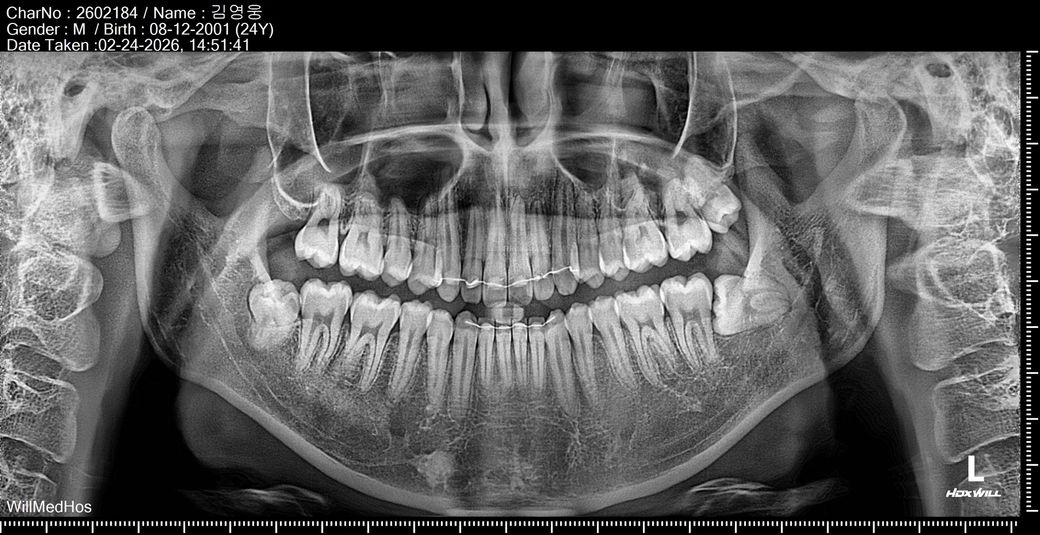

치아교정후 오른쪽 송곳니 안닿음 해결방법 궁금합니다

트랙션장치 후 치아교정 했는데 마무리할때 오른쪽 송곳니가 매우 닳아있어 군기능교합이였고 왼쪽 송곳니는 길었었습니다 그래서 오른쪽 송곳니 레진으로 견치유도를 만들고 보니 왼쪽 송곳니는 안닿았는데 오히려 의사가 freeway space를 만들어야 한다며 왼쪽 송곳니를 갈아버렸었습니다 현재 왼쪽으로 물면 치아중심선이 왼쪽으로 살짝틀어지면서 4번치아끼리 물리는 느낌입니다

어떻게 해결하면 좋을까요 현재 심스탁 찍어보면 오른쪽 송곳니는 한포인트정도 닿고 왼쪽 송곳니는 아예 닿지않습니다